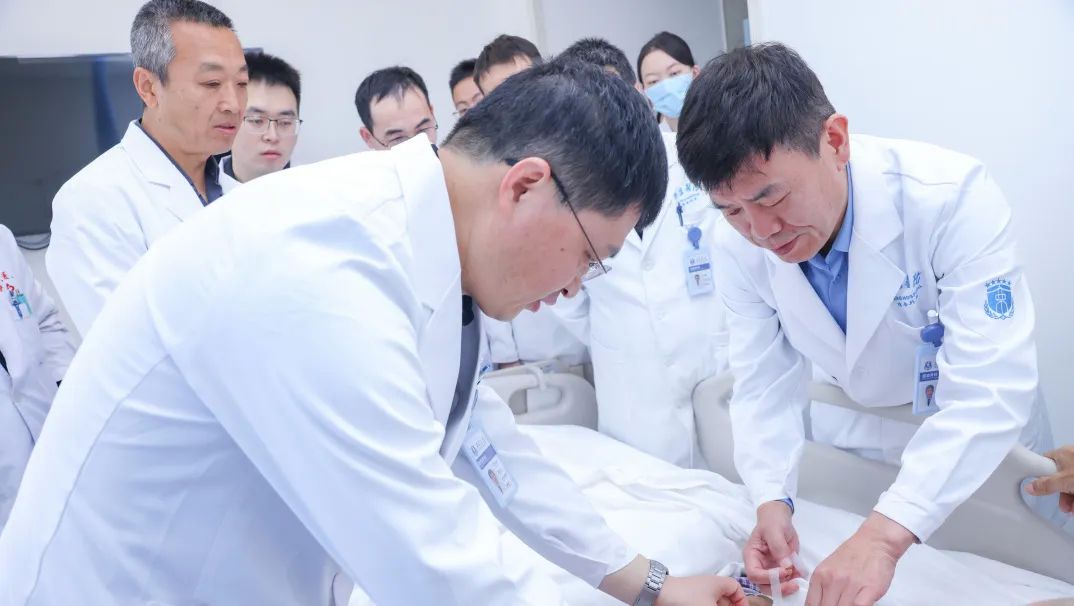

经过7个学科、11位专家

历时27天精心治疗

在医务处协调下,综合外科牵头血管内分泌外科、输血科、麻醉科、放射诊断科、重症医学科、手术室等多学科专家共同为老李会诊,商讨手术预案、围术期管理方案。

3月11日,老李被推进手术室。岳树强教授、刘正才副教授、李霄副主任医师等精准施术。术中探查结果和术前腹部影像、三维重建影像资料,均证实患者腹部脂肪肉瘤同样起源于左肾脂肪囊。

时间一分一秒流逝,在团队默契协作下,难题逐个攻破。患者左侧腹膜与肿瘤黏连,团队小心游离,采用线手套将肿瘤整体推向左侧,显露右侧根部并寻找血管边界,继而以重要大血管为指引,显露、解剖、裸化“下腔静脉、腹主动脉、左肾动静脉”至左右侧髂血管,最终完整切除肿瘤,手术历时4小时45分钟顺利结束。术中出血仅1700ml,输注RH+B型去白细胞悬浮红细胞10U、病毒灭活冰冻血浆1350ml。